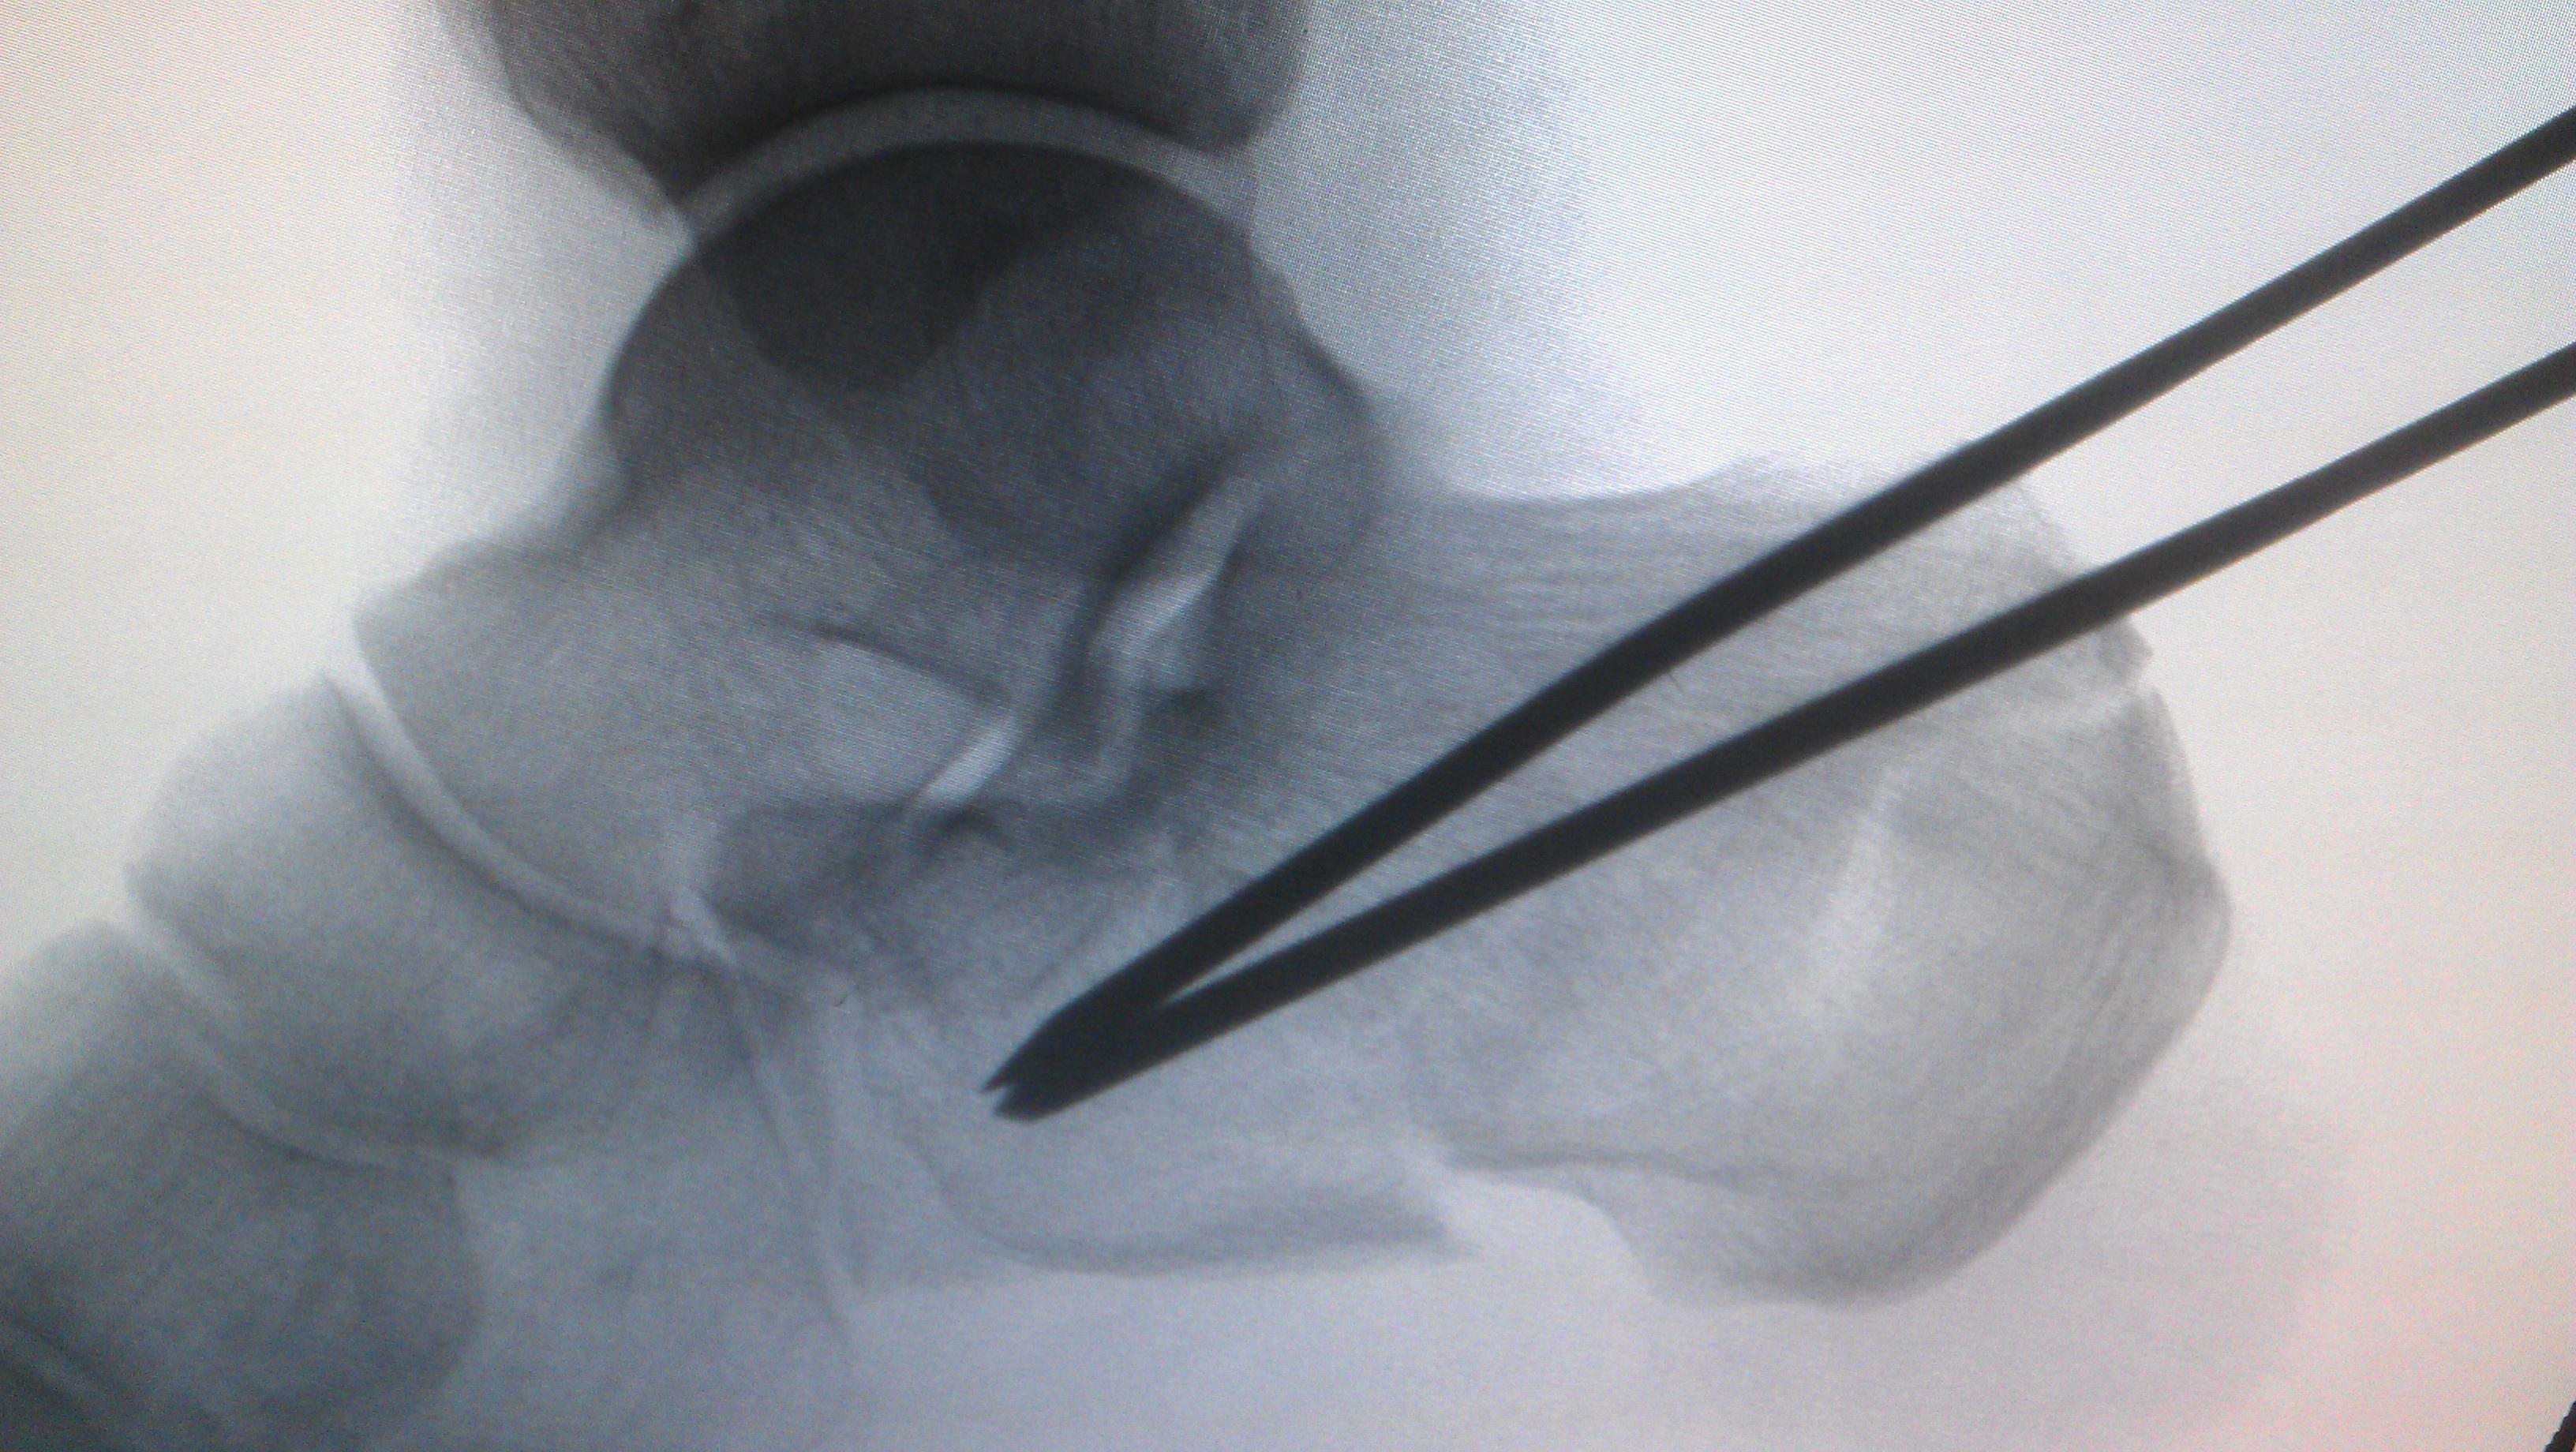

微创撬拨复位空心钉固定治疗跟骨骨折

图片尺寸2173x1787